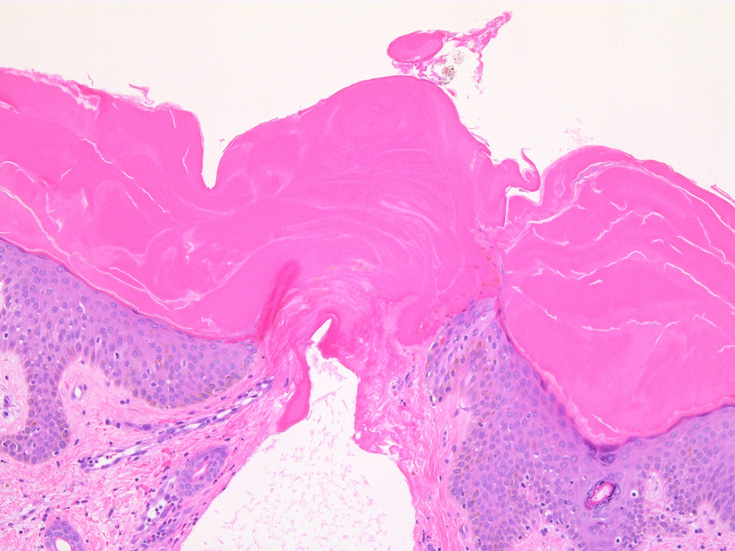

IWT-case01 66yo male. 3週間前(!)南アルプスに登山. 腹部皮膚のイボ様腫瘤に気づき来院。

マダニと思われる虫体を皮膚ごと切除した。

(case02の皮膚表面にみられる硝子様の層がそれに相当するようです。)